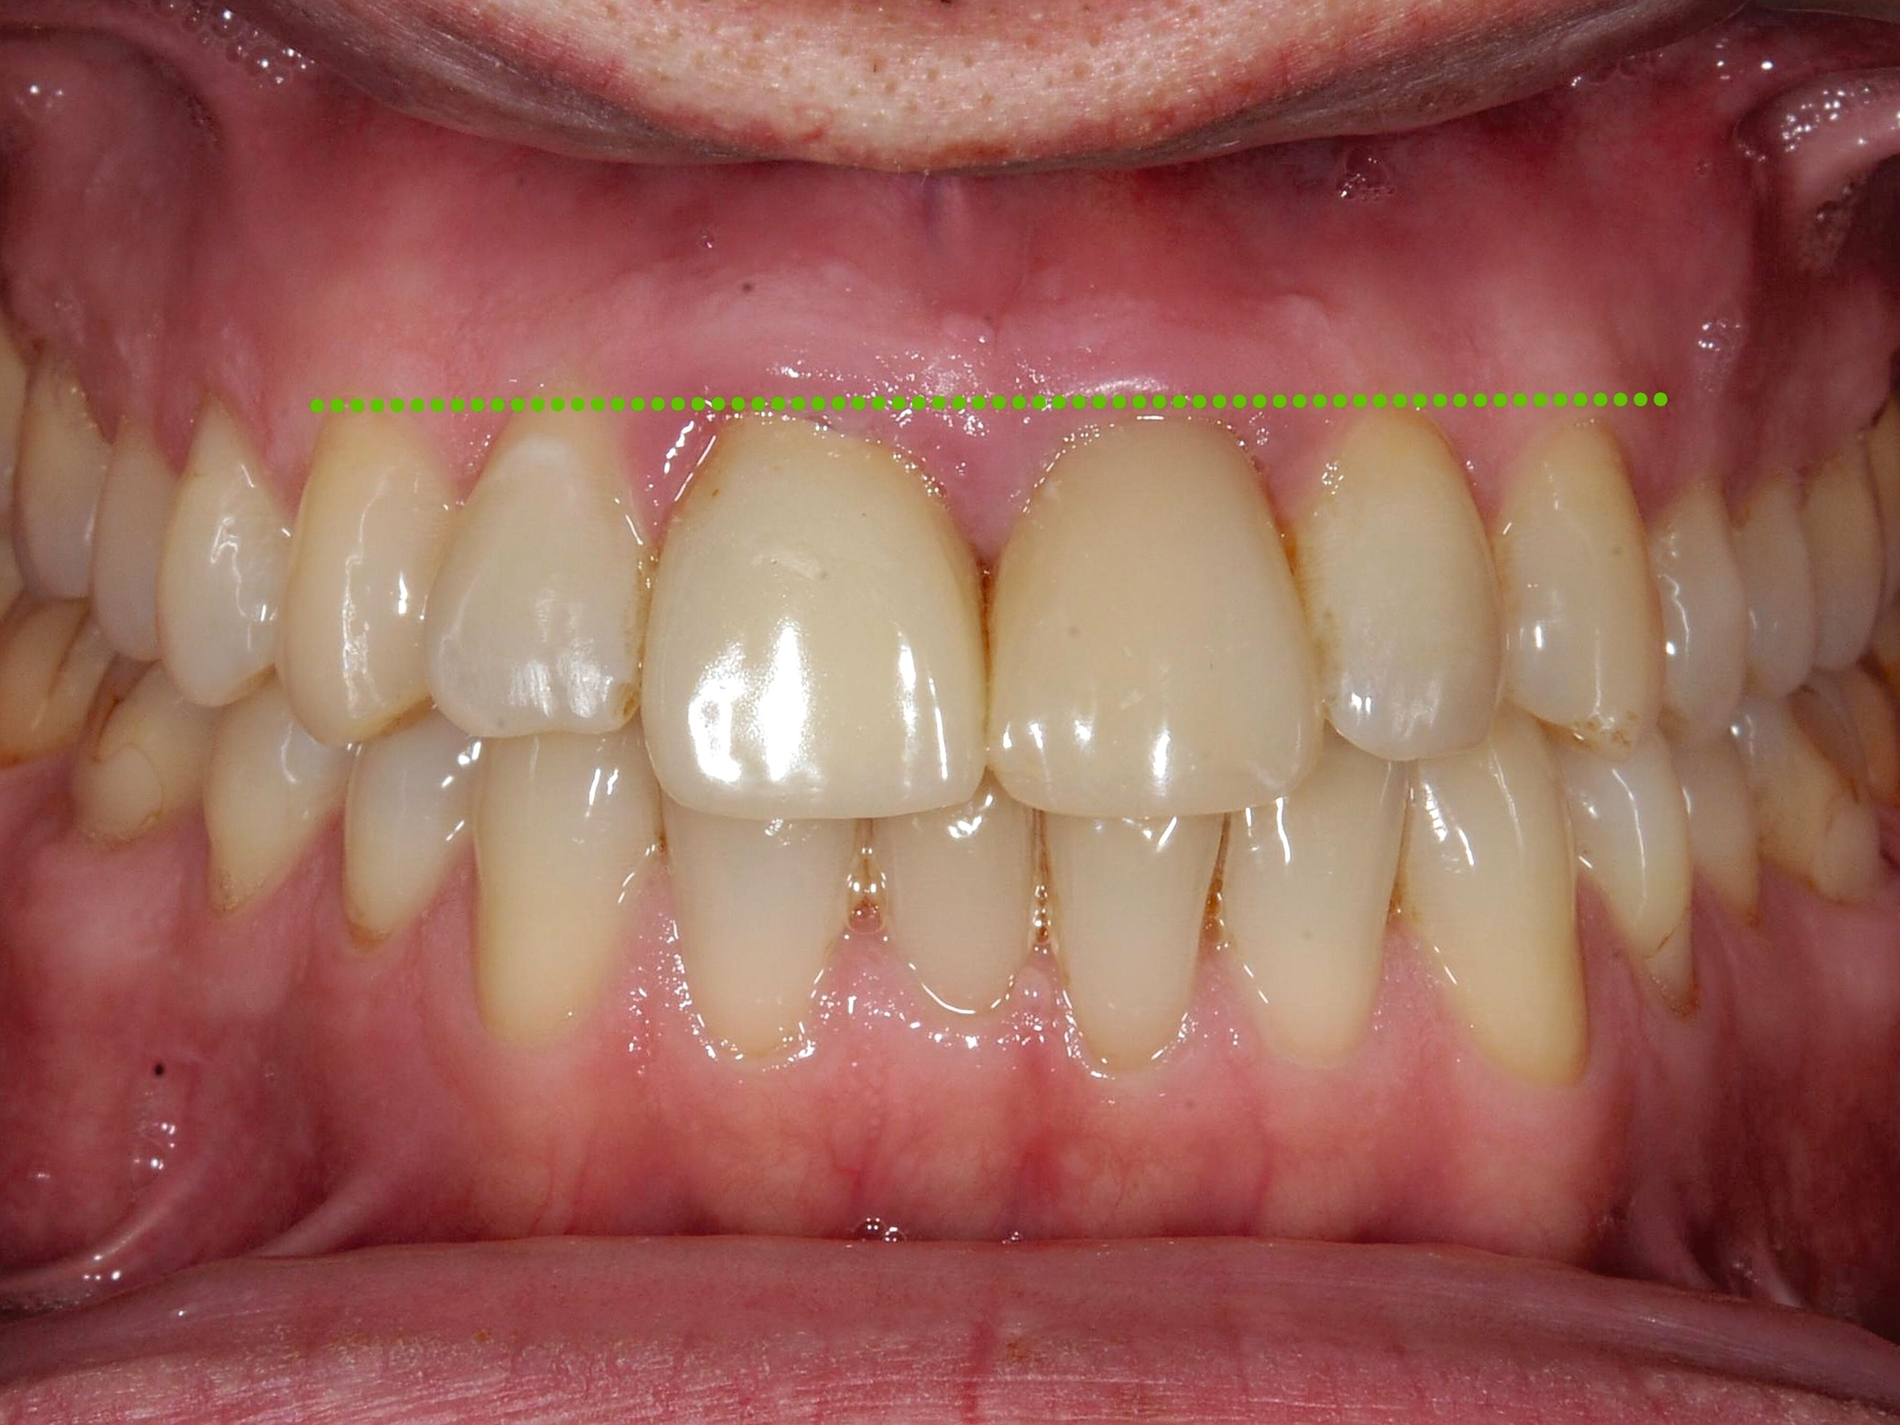

Beispielsweise kann durch eine kieferorthopädische Mesialisation nicht traumatisierter Nachbarzähne auch im wachsenden Kiefer ein traumatisch bedingtes Knochendefizit günstig beeinflusst werden [Pontoriero et al., 1987; Prapas et al., 2008; Stenvik und Zachrisson, 1993] (Abbildung 4).

In beiden Fällen kann insbesondere bei Patienten im Wechselgebiss beziehungsweise im frühen permanenten Gebiss, das heißt noch in der Wachstumsphase der Kiefer, der kieferorthopädische Lückenschluss als primäre Therapieoption geprüft werden. Bei Erwachsenen sind kieferorthopädische Zahnbewegungen ebenfalls noch möglich; insofern kann ein kieferorthopädischer Lückenschluss individuell ebenfalls geprüft werden, auch wenn hier sicherlich häufig eher prothetische Maßnahmen indiziert sind.